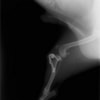

アメリカンコッカースパニエル 5歳

半年にわたる左後肢の跛行が認められるとのことで来院されました。触診にて左膝関節の疼痛、内側部の腫脹、膝蓋骨の内方脱臼を認めました。レントゲン検査にてfat pad signを伴う関節炎が認められたことから、前十字靭帯断裂と膝蓋骨内方脱臼( GradeⅢ)の併発と診断し、手術を行いました。術中の関節鏡検査にて前十字靭帯の完全断裂を確認、関節液検査にて感染を除外した後、TPLOと、滑車溝形成を始めとした膝蓋骨脱臼整復術を実施いたしました。

術前側面像

術後側面像

術前に25°であったTPAは、TPLO実施により7°に矯正されました。症例の歩行状態は良好です。